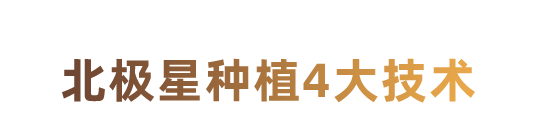

适宜安心 3D导板精确掌控种牙位置

- 安心性

- 精准性

微创不缝合

手术时间短

在导板辅助下可避免医生经验误差,掌控种植角度和深度,减少创伤,有效避开神经、血管等危险部位。